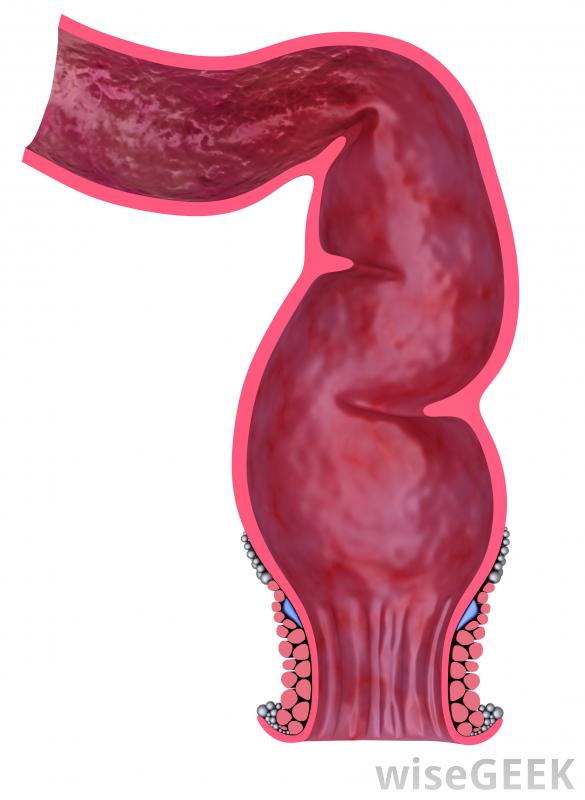

檢查結腸的異常和息肉通常需要一種特殊的診斷方法,即鋇灌腸或低G.I.(胃腸道)檢查。由于標準的x射線圖像不能提供清晰的結腸等軟組織的圖像,必須使用對比劑來提供更清晰的圖像在鋇灌腸中,這種對比劑是一種叫做硫酸鋇的金屬粉末。標準的x射線不能像結腸一樣捕捉到軟組織的良好圖像,因此必須使用對比劑在鋇灌腸開始之前,病人通常需要保持一個干凈的液體飲食,以清除結腸中殘留的糞便。可以使用標準灌腸來確保結腸盡可能的干凈。如果不清除糞便,糞便物質會擋住結腸某些部分的視野。一旦病人做好準備,他或她穿著醫院的長袍,被帶到一個檢查室。通過直腸進行鋇灌腸鋇灌腸的過程是從將硫酸鋇懸浮液通過直腸注入病人的結腸開始的。這是一種眾所周知的不舒服的體驗,在使用硫酸鋇時,許多病人會感到飽脹感或想排便一個小氣球可以防止造影劑從直腸中漏出。一旦硫酸鋇被充分分配,放射科醫生可能會要求病人采取幾種不同的體位來覆蓋結腸的每一個部分,甚至可以對病人的骨盆或腹部施加一些直接的壓力,以確保最大限度的覆蓋注射和調整硫酸鋇后,放射科醫生從不同角度拍攝了許多x射線圖像。由于硫酸鋇在標準x光片上呈白色,所以任何暗區都要仔細檢查是否有異常跡象。如果需要更多的清晰度,可以在最初的鋇灌腸后注射空氣進入結腸。病人可以在私人浴室里排出硫酸鋇,但通常有足夠的殘留物來為第二次檢查提供對比。并非所有的鋇灌腸程序都需要使用空氣來給結腸充氣,但人們相信改進的對比度值得額外的時間和精力小息肉可能很難通過標準的鋇灌腸來發現。一般鼓勵鋇灌腸檢查的標準年齡是50歲,盡管有結腸直腸疾病家族史的人可能會選擇早一點做一次。大多數人都能承受在鋇灌腸檢查之間等待5-10年,但是那些表現出其他結直腸癌癥狀或首次檢查結果有疑問的患者可能需要更頻繁地接受這種手術,鋇灌腸被認為是完全結腸鏡檢查的一種微創的替代方法,可能需要在麻醉下進行鋇灌腸可以提供許多與結腸鏡檢查相同的答案,而不會增加不適和恢復時間。僅通過標準鋇灌腸很難發現較小的息肉。